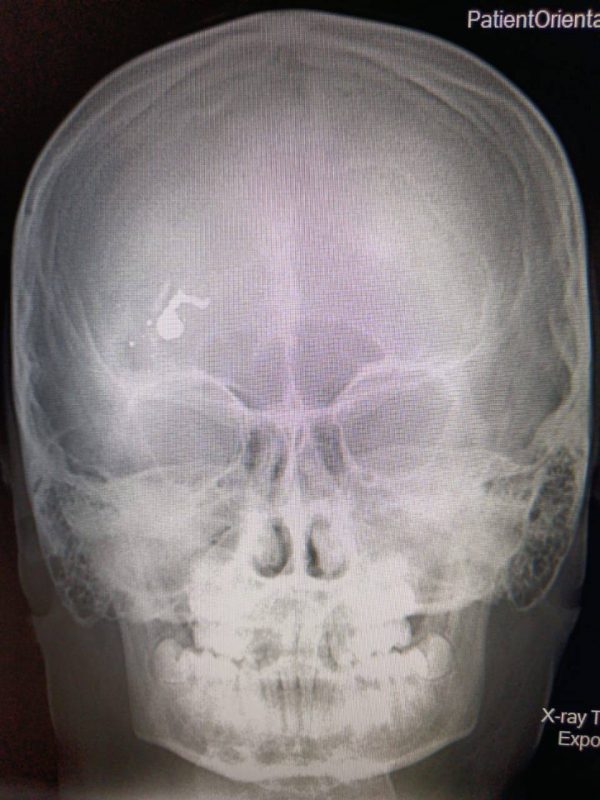

Как сообщается в telegram-канале регионального минздрава, пуля находилась в лобной доле черепа ребенка. После того, как фельдшеры перевезли мальчика в Саратов, бригада врачей приступила к срочной операции. Извлечение пули и осколков длилось пять часов.